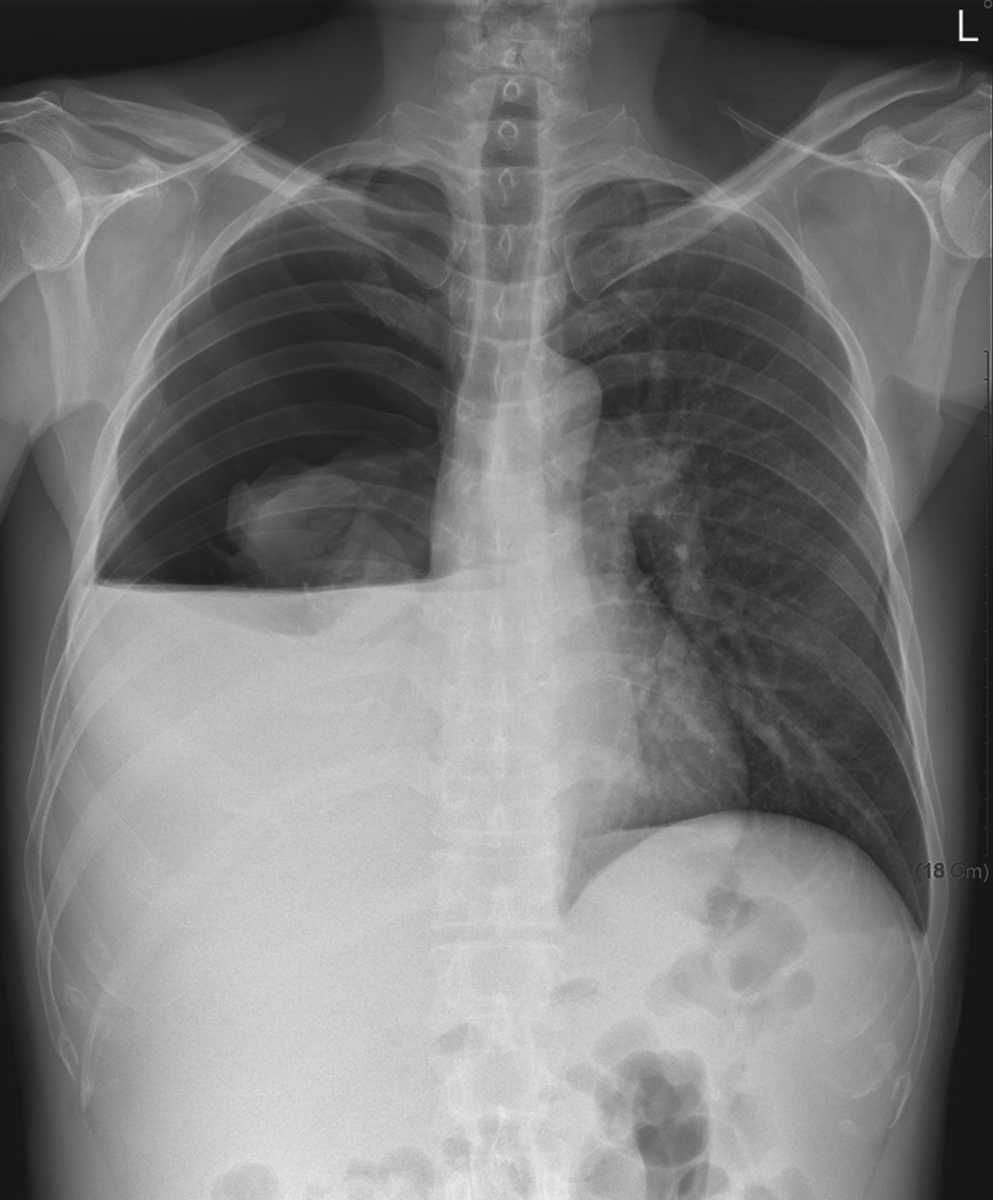

A 47-year-old man with a history of cirrhosis associated with alcohol abuse presented with a 2-day history of shortness of breath.

What’s the Diagnosis ?